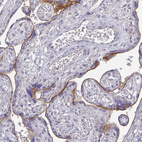

Immunohistochemical staining of human HER2-positive breast cancer shows strong membranous positivity in tumor cells.